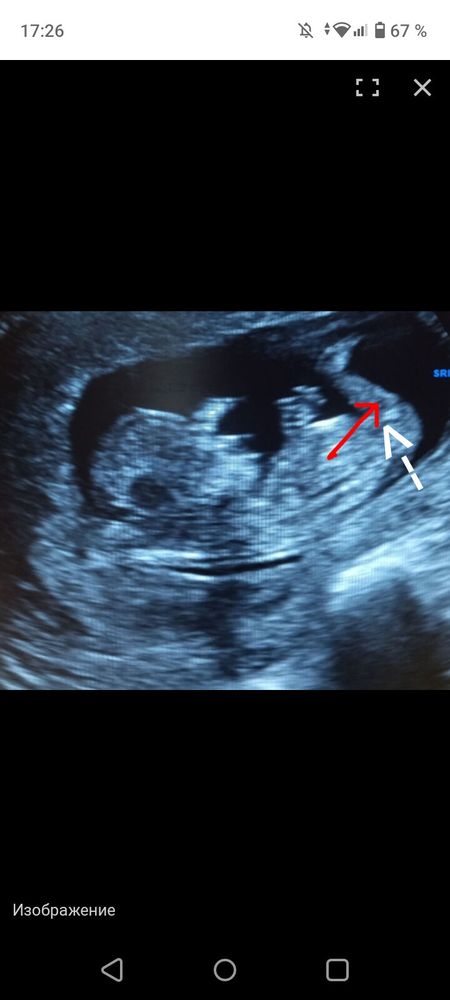

Изображение Ольга,

Family, я не понимаю. Что это вы линиями обозначили?)

Ольга, половой бугорок и спину Изображение

Ольга, да, вы ножку отметили. Я предполагаю, что бугорок чуть ниже. И она не направлена вверх Изображение